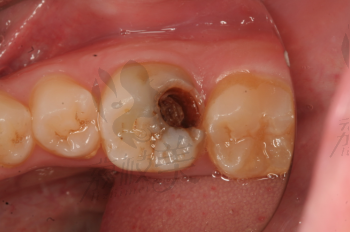

摘要:面對牙齒疼痛,特別是牙爛大窟窿帶來的困擾,需及時采取應(yīng)對措施。建議盡快就醫(yī),進行專業(yè)牙齒檢查和治療。日常護理方面,注意口腔衛(wèi)生,定期刷牙,使用牙線和漱口水清潔口腔。飲食避免過冷過熱刺激,減少糖分攝入,以防細菌滋生。如需緩解暫時疼痛,可服用止痛藥,但不可長期依賴。預防牙爛,定期口腔檢查至關(guān)重要。

牙齒疼痛是常見的口腔問題之一,而牙爛了個大窟窿晚上痛更是讓人難以忍受,這種情況不僅影響生活質(zhì)量,還可能引發(fā)其他口腔疾病,本文將為您解析牙爛窟窿的原因,并探討應(yīng)對方法和預防措施。

1、齲齒:齲齒是牙齒爛掉的主要原因之一,長期不注意口腔衛(wèi)生,細菌滋生導致牙齒逐漸腐蝕。